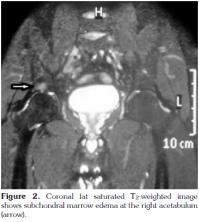

The typical MRI findings of AS are enthesisitis and ankylosis. However, at the very early stage of the disease, synovitis and and subcortical bone marrow edema are important diagnostic features. A number of studies have shown that subchondral bone marrow edema developes as a result of inflammation in various sites such as the sacroiliac joints, femoral heads, and the shoulders.[14-16] The sign of early involvement in AS is subcortical edema. Subcortical edema may be seen at the femoral head, symphisis pubis, and other sites of enthesis (Figure 1, 2). Histological studies have shown that the bone marrow edema in AS is in correlation with osteitis.[17] The femoral head bone marrow edema in AS differs from the diffuse form seen in septic arthritis, and it is more focal, frequently encountered in tendinous and ligamentous insertion sites. A similar pattern was present in the cases of our study (Figure 3). In one study, it was reported that 23% of cases with juvenile AS demonstrated subcortical edema at the symphisis pubis.[17] In our study, no bone marrow edema was encountered at the sites of the symphisis pubis of the patients. This fact may be due to the limited number of the patients enlisted in our study, and also to the difference in the patient age groups between our study and the study mentioned above.

The site of insertion of the tendons, ligaments, joint capsules, and the fascia is known as the enthesis.[18,18] While ultrasonography can only detect soft tissue alterations, MRI can also demonstrate intraosseous abnormalities.[20-24] In our patient group, six patients (13%) had bone marrow edema. Three of these patients had bone marrow edema at the acetabulum, and the other three at the lateral aspects of the femoral heads and the tuberculum majus.